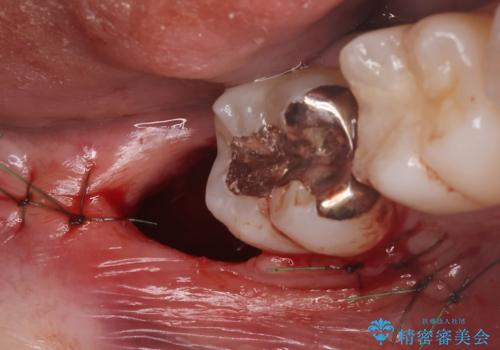

- 親知らずが痛くて抜きたいと来院。

CTを撮影し、神経の位置など確認し安全なことを確認して抜歯を行いました。

抜歯は当日行う事が出来ます。